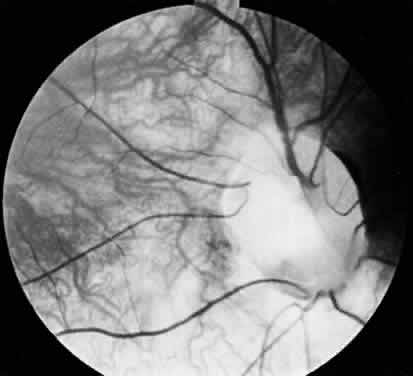

FALCIFORM RETINAL FOLDS

The falciform retinal fold extends from the optic disc to the ciliary body, usually in the inferotemporal quadrant.2 It may be bilateral and symmetrically distributed, and it is typically associated with persistent remnants of the hyaloid artery. The falciform fold usually occurs in an otherwise healthy eye, although it may cause a tentlike detachment of the retina.89–91 The pathogenesis of this anomaly may involve traction on the retina, which is caused by persistence of hyaloid vessels and by elements of the primary vitreous that become attached to the inner layer of the optic cup. Falciform retinal folds may also occur secondary to retinopathy of prematurity (ROP), foreign bodies, and granulomatous inflammation.